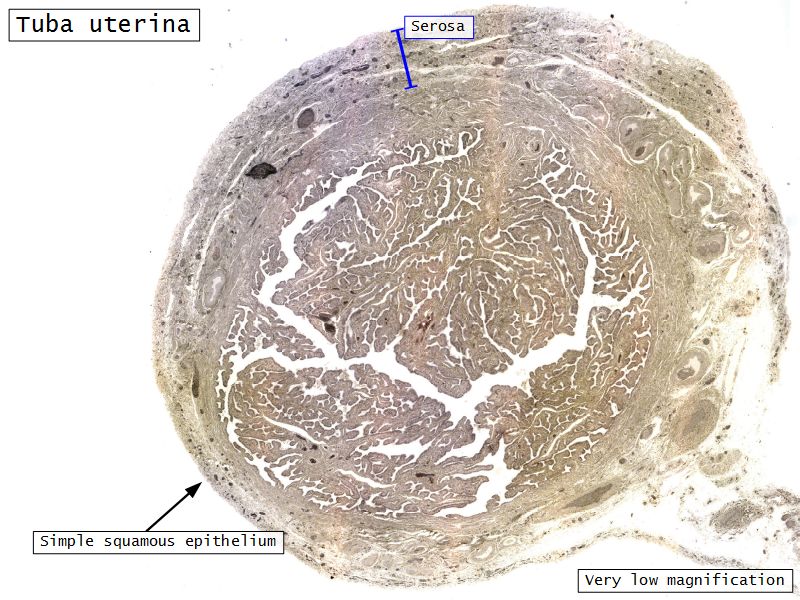

Tuba uterina

Slide 97

Also:

OviductFallopian tube

Uterine tube

Tuba uterina

- Muscular tube

- Most frequent site of fertilization

- Conveys zygote to uterus

- Four regions

- Three layers

Four regions

- Infundibulum

- Ampulla

- Usual site of fertilization

- Isthmus

- Pars interstitialis

- Passes through wall of uterus

Three layers

- Mucosa

- Muscular layer

- Serosa

Serosa

- Simple squamous epithelium

- Contains

- Blood vessels

- Lymphatics

- Nerves